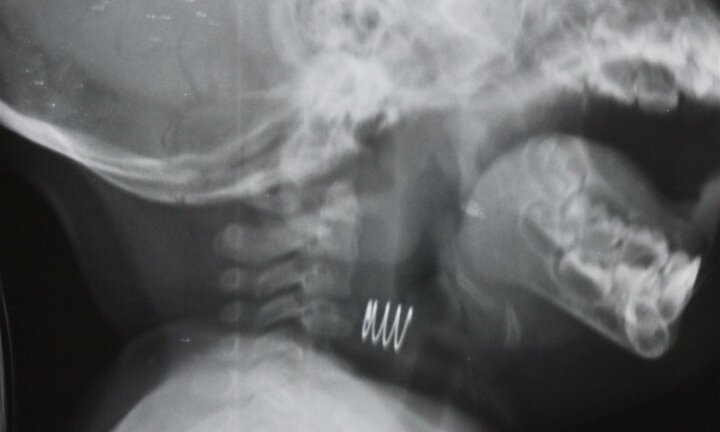

Chiếc lò xo han gỉ mắc trong thực quản bé gái 7 tháng tuổi

Bệnh nhi Dương Minh Q. (7 tuổi) tại Vạn Phúc, Hà Đông, vào khoa Tai mũi họng, Bệnh viện đa khoa Hà Đông trong tình trạng đau họng, nuốt vướng, nuốt đau, không ăn uống được.